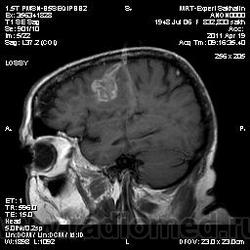

склоняюсь к кровизлиянию в левой теменной долей, начало перехода острой стадии в раннюю подострую( по периферии определяется повышение МРС по Т1 ВИ -метгемоглобин). Справа -старые кортикальные постишемческие глиозно-атрофические изменения. Контрастируется , вероятно за счет формирования участков ангионеогенза.

На фоне ДЭП изменений МР-картина ОНМК по ишемическому типу в бассейне ЛСМА с участками геморрагического пропитывания. Аналогичный участок но в более поздней фазе в задних конвнкситальных отделах правой теменной доли.

Постконтрастные сканы есть.После надписи"постконтраст".

тогда да, не особо в геморрагический ОНМК укладывается

При просмотре исседования на постконтрастных сканах выскакивает надпись "Омнискан"-сама недавно заметила.

Пардон, в упор не вижу где Омнсикан написано. И в стандартном расположении экрана GE нету "+С".

Как вариант хочу предложить на рассмотрение грибковое поражения головного мозга или токсоплазмоз. В таком случае полностью укладывается изменение сигнальных характеристик и на нативе и на постконтрастных сканах. Можно проверить на иммуносупресивные состояния, на наличие грибкового эндокардита (Узи сердца).

На опухоль не тянет. Для инфаркта и банальной гемморрагии не характерен тип накопления контраста на мой взгляд.